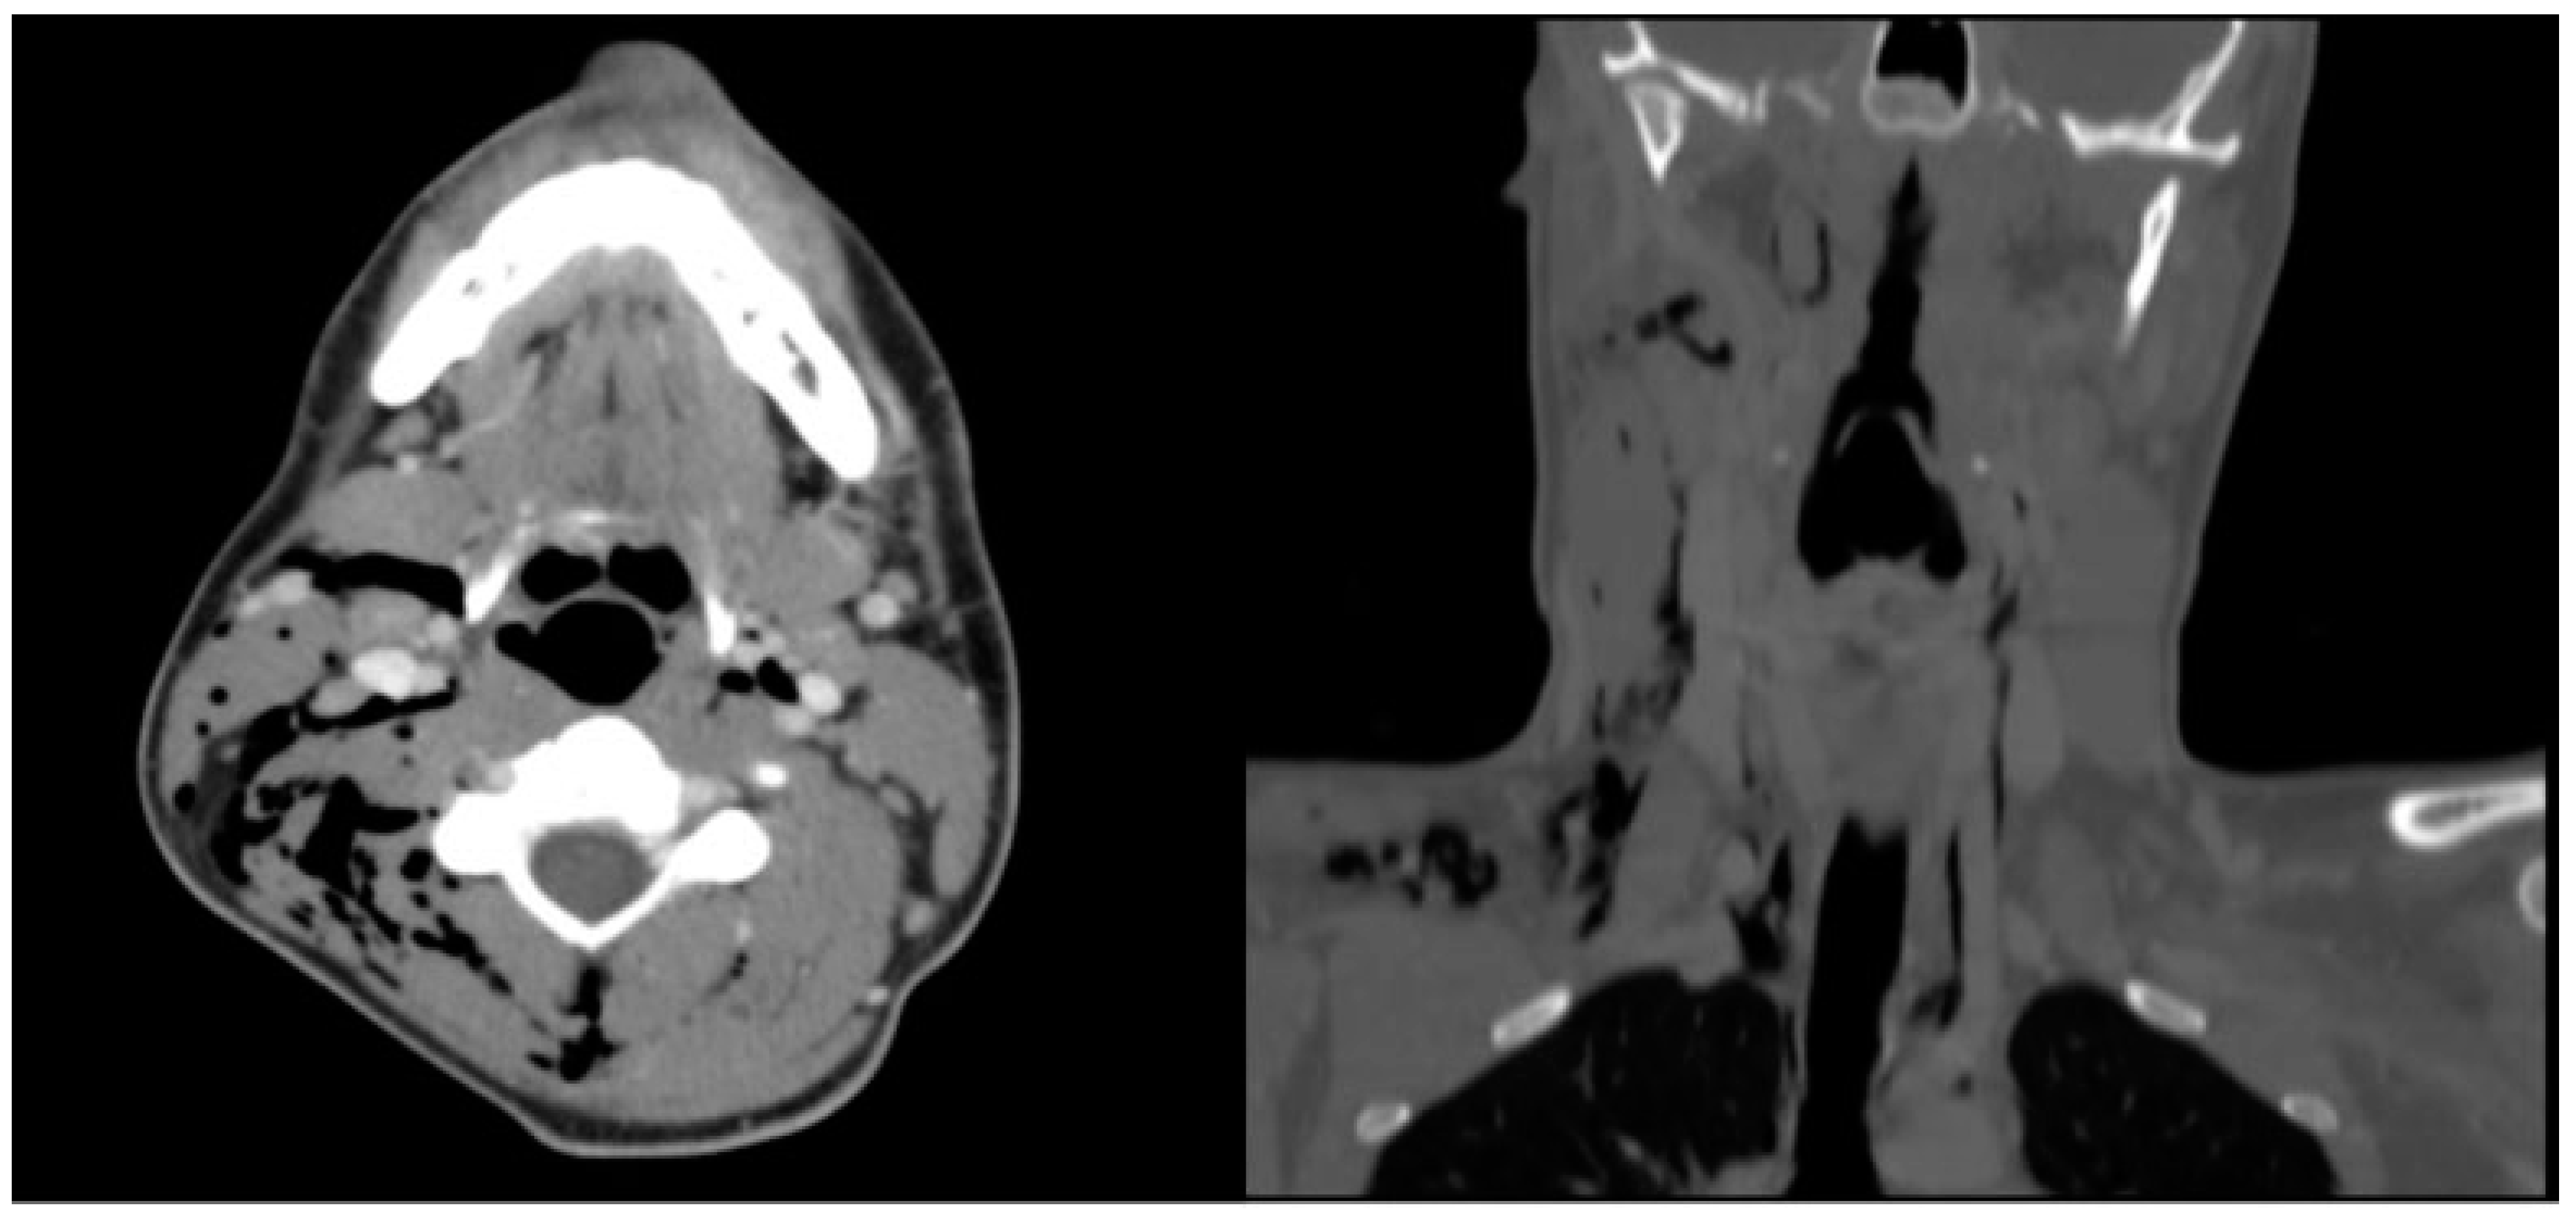

Neck CT scan revealed extensive subcutaneous and deep cervical emphysema extending from the posterior occiput caudally into the superior mediastinum. The air extended into the parapharyngeal spaces, bilateral carotid spaces, and intramuscularly into the right sternocleidomastoid muscle (Figure 3).

Figure 3. (Left) Subcutaneous air in the right parapharyngeal space, along bilateral carotid sheaths, and within the right sternocleidomastoid muscle fibers. (Right) Gas extension inferiorly from bilateral carotid sheaths into the mediastinum.